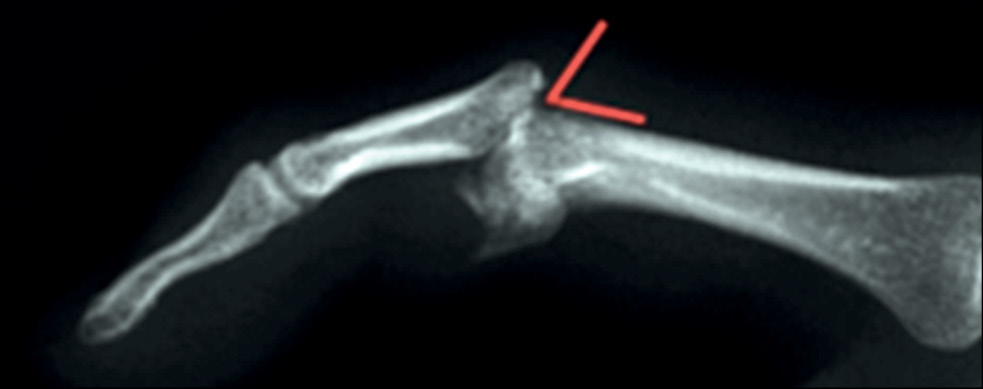

Переломовывихи ПМФС являются следствием двух основных механизмов: отрыва или смещения при осевом ударе. Направление смещения используется для классификации травмы: тыльный переломовывих (то есть тыльный вывих с переломом ладонного края средней фаланги) (рис. 4) или ладонный переломовывих (то есть ладонный вывих с переломом тыльного края средней фаланги). Третья категория — это травма пилона, при которой в перелом вовлечены как ладонный, так и тыльный края основания средней фаланги. При разгибании в ПМФС ладонная пластинка натягивается. При гиперэкстензии повреждение ладонной пластинки происходит в виде разрыва толщи пластинки либо отрыва от основания средней фаланги. Отрывные переломы различаются по размеру костного фрагмента и его смещению, но, как правило, без фрагментации отломка. Осевая нагрузка, приложенная к пальцу при его сгибании, приводит к столкновению с головкой проксимальной фаланги. При сгибании в ПМФС осевая нагрузка на среднюю фалангу приводит к перелому ладонного края её основания. При таком переломе теряется стабилизирующая функция ладонной пластинки и происходит тыльное смещение фаланги [13].

Рис. 4. Схема механизма травмы переломовывиха ладонного края основания средней фаланги.

Fig. 4. Schematic diagram of the base of the middle palmar edge phalanx fractured-dislocation injury mechanism.